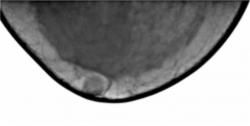

Протокол исследования. В левой молочной железе в верхнем наружном квадранте определяется снижение прозрачности железистого треугольника за счет избыточного развития фиброзной ткани, на фоне чего определяются очаговые уплотнения – по всей видимости, мелкие фиброаденомы. Аналогичные очаговые уплотнения в верхнем медиальном квадранте (1 – снимок в прямой проекции, 2 – снимок в боковой проекции). Передний контур железистого треугольника неровный. В верхнем наружном квадранте, на фоне премаммарного пространства определяется объёмное образование средней интенсивности, однородной структуры, с нечетким контуром, окруженное просветлением – «поясок безопасности», оттесняющее и сужающее молочный синус медиально. 3, 4 – участок, выделенный «навигатором» для более детального анализа патологического образования. 5 – для сравнения приведено обычное расположение молочного синуса.

3. участок, выделенный «навигатором» для более детального анализа патологического образования